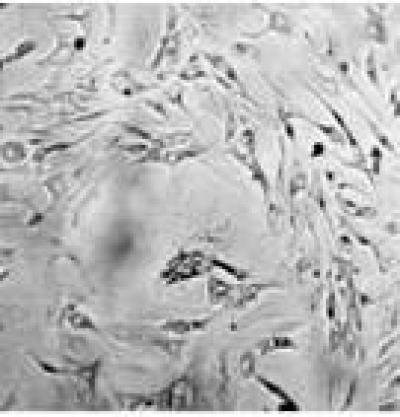

In the central nervous system, nerve cells adhere to the extracellular matrix. Type I collagen is the major class of insoluble fibrous proteins in the extracellular matrix. A previous study has shown that neural stem and progenitor cells, cultured on collagen matrices, are able to expand actively and generate neurons. Collagens can be classified into hydrolyzed and non-hydrolyzed collagens, or two-dimensional and three-dimensional collagens. Which form of collagen is suitable for nerve cell culture? Dr. Mohsen Fathi Najafi and colleagues from Mashhad University of Medical Science, Iran, investigated the effects of hydrolyzed and non-hydrolyzed collagen and two-dimensional and three-dimensional collagen matrices on cell survival, attachment and neurite outgrowth of primary cultured nerve cells using 3-[4,5-dimethylthiazol-2-yl]-2,5-diphenyltetrazolium bromide co-lorimetric assay and inverted microscopy. Hydrolyzed collagen facilitated nerve cell survival and neurite outgrowth, but it had no obvious influences on cell attachment. In contrast, non-hydrolyzed two-dimensional collagen matrix had no obvious effects on neurite outgrowth. These findings, published the Neural Regeneration Research (Vol. 8, No. 23, 2013), suggest that hydrolyzed collagen is an ideal nerve cell culture media.